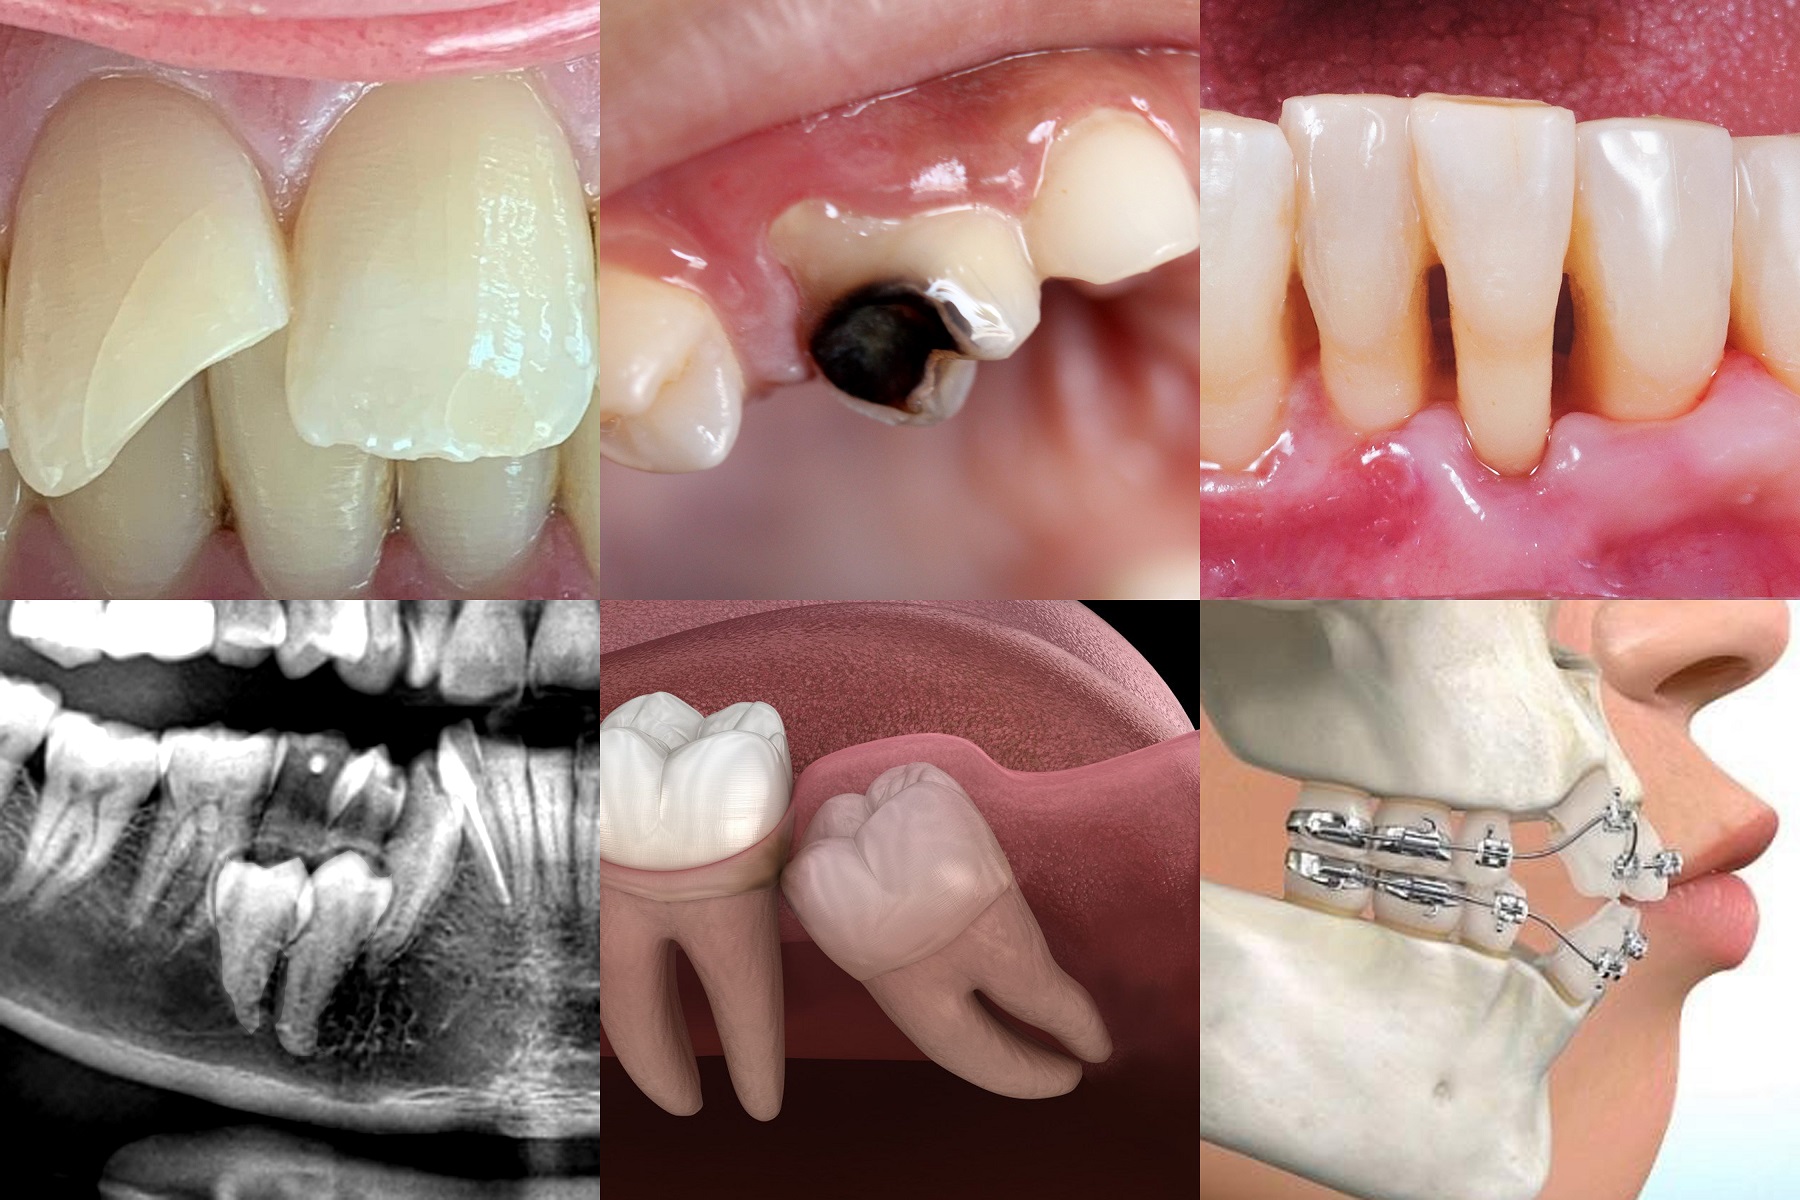

Extraction & Oral Surgery

Oral surgery encompasses a range of procedures focused on treating complex issues of the teeth, jaws, and surrounding tissues. While our primary goal is always to save your natural teeth, there are times when an extraction or surgical intervention is the most effective way to eliminate pain and restore your long-term oral health.

Whether you require the removal of an impacted wisdom tooth or a surgical preparation for implants, our team utilizes the latest diagnostic imaging and minimally invasive techniques. We prioritize your comfort at every stage, offering advanced sedation options to ensure a stress-free and painless experience.

• Safe removal of severely damaged or decayed teeth.

• Expert management of impacted wisdom teeth.

• Bone grafting and sinus lifts for implant readiness.

• Surgical treatment for oral infections and abscesses.

Oral surgery is a highly specialized field that addresses issues that simple dentistry cannot. Our clinicians are trained to handle a wide variety of surgical needs with precision and a focus on rapid healing.

• Wisdom Tooth Extraction: Preventing crowding and infection.

• Alveoloplasty: Smoothing the jawbone after extractions.

• Frenectomy: Correcting tongue-tie or lip-tie issues.

• Biopsies: Investigating suspicious lesions for peace of mind.